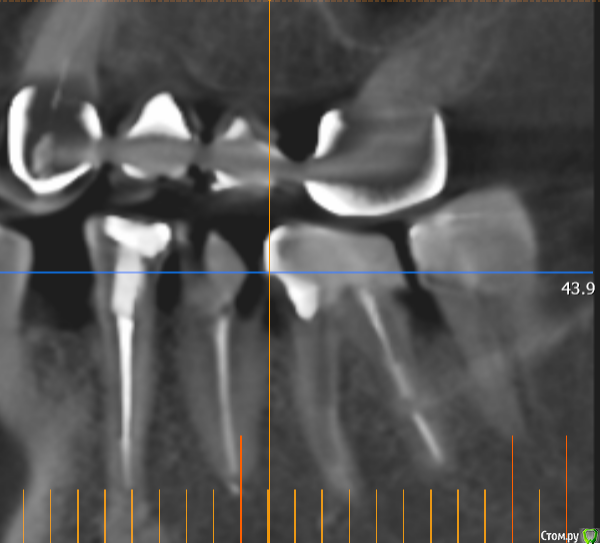

msa Опубликовано 27 февраля, 2019 Поделиться Опубликовано 27 февраля, 2019 Здравствуйте, уважаемые доктора!Прошу совета в выборе оптимального плана лечения и восстановления зубного ряда.Слева вверху (2.3-2.6) мост м/к с 1998 г(со слезами обточила здоровый красивый клык).Справа внизу был мост м/к 2006г на 4.4-4.7 (опорный моляр 4.7 + штифт в 4.5, конструкция была не очень, т.к. не отдала обтачивать под коронку клык 4.3) Через 7 лет мост слетел… От слова совсем.В н/вр пытаюсь понять, нужно ли бороться за премоляр 3.5 Или однозначно удалять? Можно ли сохранить 3.6 с помощью культевой вкладки?Какие варианты оптимального замещения низа справа 4.4-4.7? Корни пока не удаляю. Жизнеспособен ли верх 1.4-1.6? (пломбам больше 20 лет) Скриншоты из КТ от 25.02.19 ОПТГ не делалаСпасибо!С уважением, Марина Ссылка на комментарий

msa Опубликовано 1 марта, 2019 Автор Поделиться Опубликовано 1 марта, 2019 Результат очного осмотра:-верх справа/ 1.4, 1.5, 1.6 лечить, вкладки, коронки (если выдержат)-низ справа/ 2 импланта в области 4.5 и 4.7 ( кость нормальная) Очень расстроил низ слева / 3.5 -удаление, 3.6 -удаление/ имплантыНеужели однозначно удалять все? Please help me! Ссылка на комментарий

kramer Опубликовано 1 марта, 2019 Поделиться Опубликовано 1 марта, 2019 По таким срезам сложно сказать, к тому же без осмотра. Раз врач сказал... Ссылка на комментарий

msa Опубликовано 1 марта, 2019 Автор Поделиться Опубликовано 1 марта, 2019 По таким срезам сложно сказать, к тому же без осмотра. Раз врач сказал...Спасибо за ответ. Срезов могу добавить(наверное, правильнее в терапии вопрос о возможном лечении зуба размещать?) Насчет "раз врач сказал..." . Это только мнение хирурга-имплантолога. Может, в терапии по иному взглянут на зубной ряд? Ссылка на комментарий